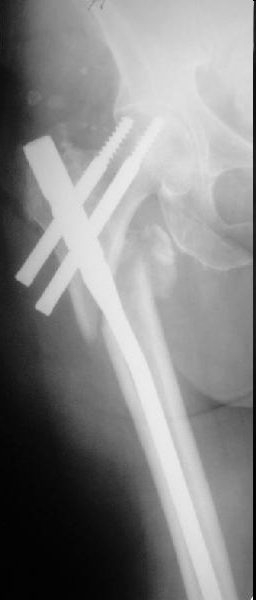

Пациентка, К., 74 лет. В марте 2013 г. упала, диагностирован многооскольчатый чрезподвертельный перелом левой бедренной кости со смещением отломков. 05.03.2013 выполнена закрытая репозиция, остеосинтез левой бедренной кости длинным бедренным гвоздем (ITST, Zimmer) со статическим блокированием отломков. Пациентка в течение 8 недель ходила при помощи ходунков с минимальной нагрузкой на оперированную нижнюю конечность. После выполнения рентгенографии отмечена тенденция к прорезыванию винта и смещение шейки бедренной кости латерально по оси винта (до стержня), нагрузка была ограничена еще на 8 недель. Через 8 недель постепенное градуированное повышение нагрузки до полной. В течение 1,5 месяцев ходила с полной нагрузкой на левую нижнюю конечность, водила автомобиль. Через 1,5 месяца стала отмечать боль в области левого коленного сустава (ранее выполнялось эндопротезирование). Данных за нестабильность компонентов не выявлено. Курсы НПВС по-началу купировали боль в области бедра, через 1 месяц стали малоэффективны. Пациентка наблюдается у невролога в связи с протрузией дисков на уровне пояснично-крестцового отдела позвоночника и периодическими обострениями остеохондороза. С диагностической целью была выполнена блокада бедренного нерва с левой стороны. Боль была полностью купирована, однако возобновилась после прекращения действия анестетика. 10.10.2013 г. пациентка выполнила рентгенографию левого тазобедренного сустава. Выявлен перелом металлофиксатора. Пациентка госпитализирована для лечения.Пациентка до травмы вела активный образ жизни, водила автомобиль. В настоящее время хочет избавиться от болевого синдрома, восстановить опороспособность левой нижней конечности, вернуться к своему обычному ритму жизни.Коллеги три основных вопроса:Какую тактику в данном случае предприняли бы Вы? Варианты удаления металлофиксатора? Чем выполнить реостеосинтез?С уважением, Ершов Дмитрий Сергеевич

Про динамизацию забыли написать. Но проблема из без нее очевидна. Типичная ошибка с "диагональным" положением гвоздя. Т.е. латеральная точка введения и направление к медиальной стенке центрального отломка. Как он должен бы располагаться - зеленая линия на картинке. Соответственно, надо пересинтезировать аналогичным имплантатом, не повторив этой ошибки. Наверно, можно в шейку в передне-заднем направлении ввести 1-2 винта в проекции канала от lag screw.

Все, что было написано по снимку со сломанным гвоздем, остается в силе. Чрезмерно латеральная точка введения, медиальное направление в центральном отломке. То есть варус не устранен, откуда все последующие проблемы. Как решать - уже написал. Конечно, есть и другие варианты реостеосинтеза (клинковая пластина, DHS, даже аппарат) - но тут вполне выполним все еще малоинвазивный реостеосинтез аналогичным гвоздем с исправлением ошибок.

Может я не все понял, создаётся впечатление, что левое бедро синтезировали правым гвоздём.